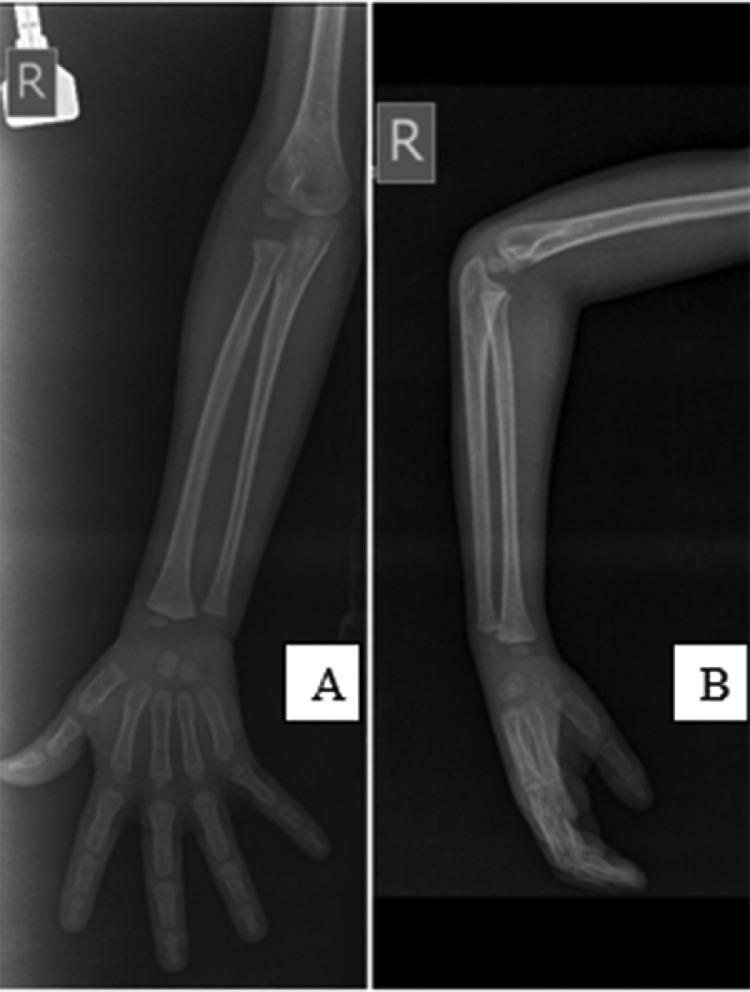

Unilateral congenital proximal radioulnar synostosis in a 4-year-old boy: A case report.

Congenital radioulnar synostosis is a rare musculoskeletal disorder of the elbow, occurring as a result of variable degree and length of the congenital fusion of the proximal radioulnar joint. Patients presents early to the hospital depending on the severity of the synostosis and its effect on elbow function. It may have psychosocial effects on the affected individuals as they grow older especially when the deformity is dramatic. Treatment may be conservative, surgical (which may have a variable degree of success) and psychotherapy.